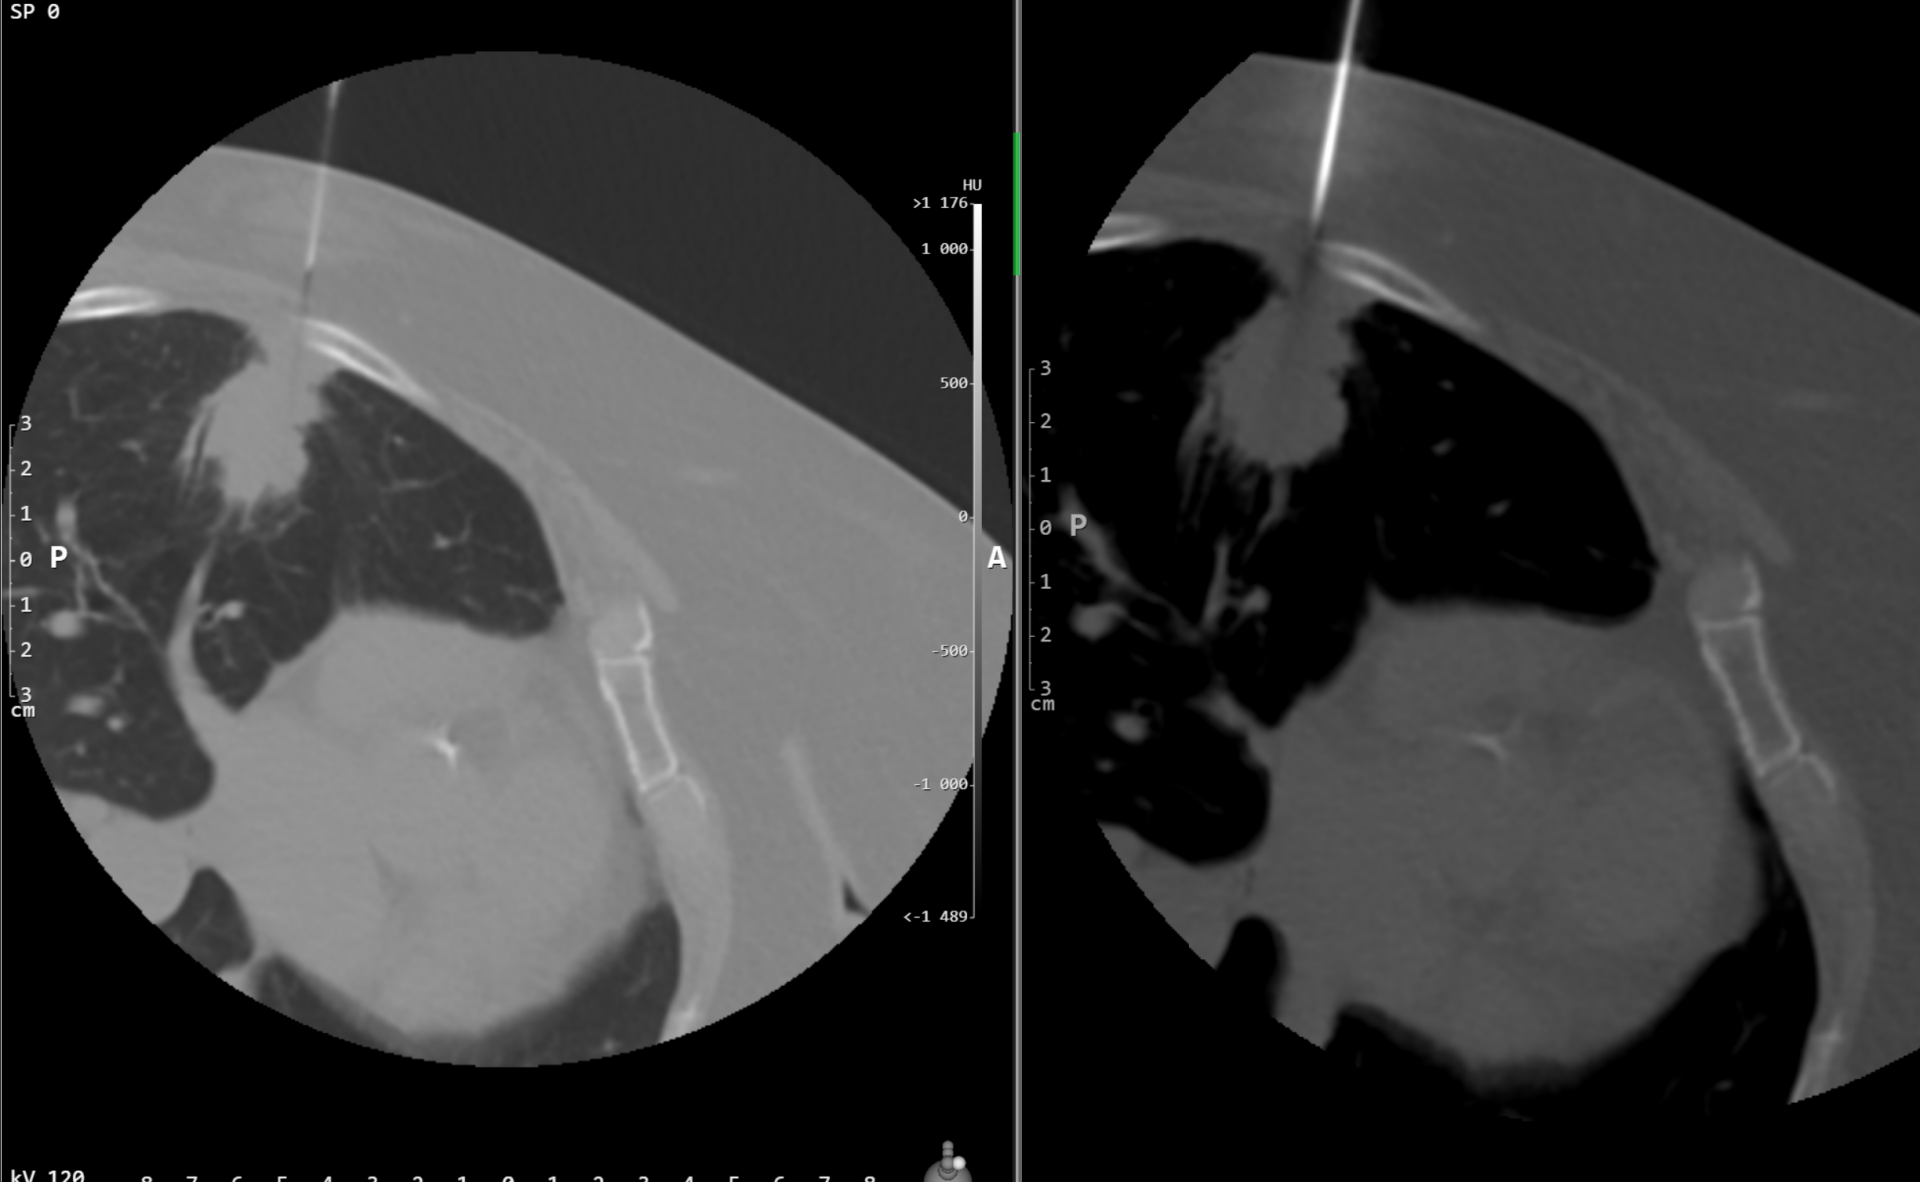

Co se vlastně při CHLSE odehrává?

Při výkonu budete ležet na břiše, a nebudete se hýbat, celý výkon trvá většinou 15 – 20 minut, výjimečně déle. Zezadu lékař zavede tenkou jehlu (tenčí než na odběr krve) do místa, kde probíhají kmeny sympatického nervstva (vedle páteře) a injektuje léčebnou směs sestávající z alkoholu, anestetika a malého množství kontrastní látky, celkové množství směsi je okolo 13 ml. Aplikace směsi může být spojena s nepříjemnými zážitky – většinou bolestmi do břicha či do zad, též se můžete celkově potit. Poté, co je směs umístěna, lékař vytáhne jehlu a místo přelepí.